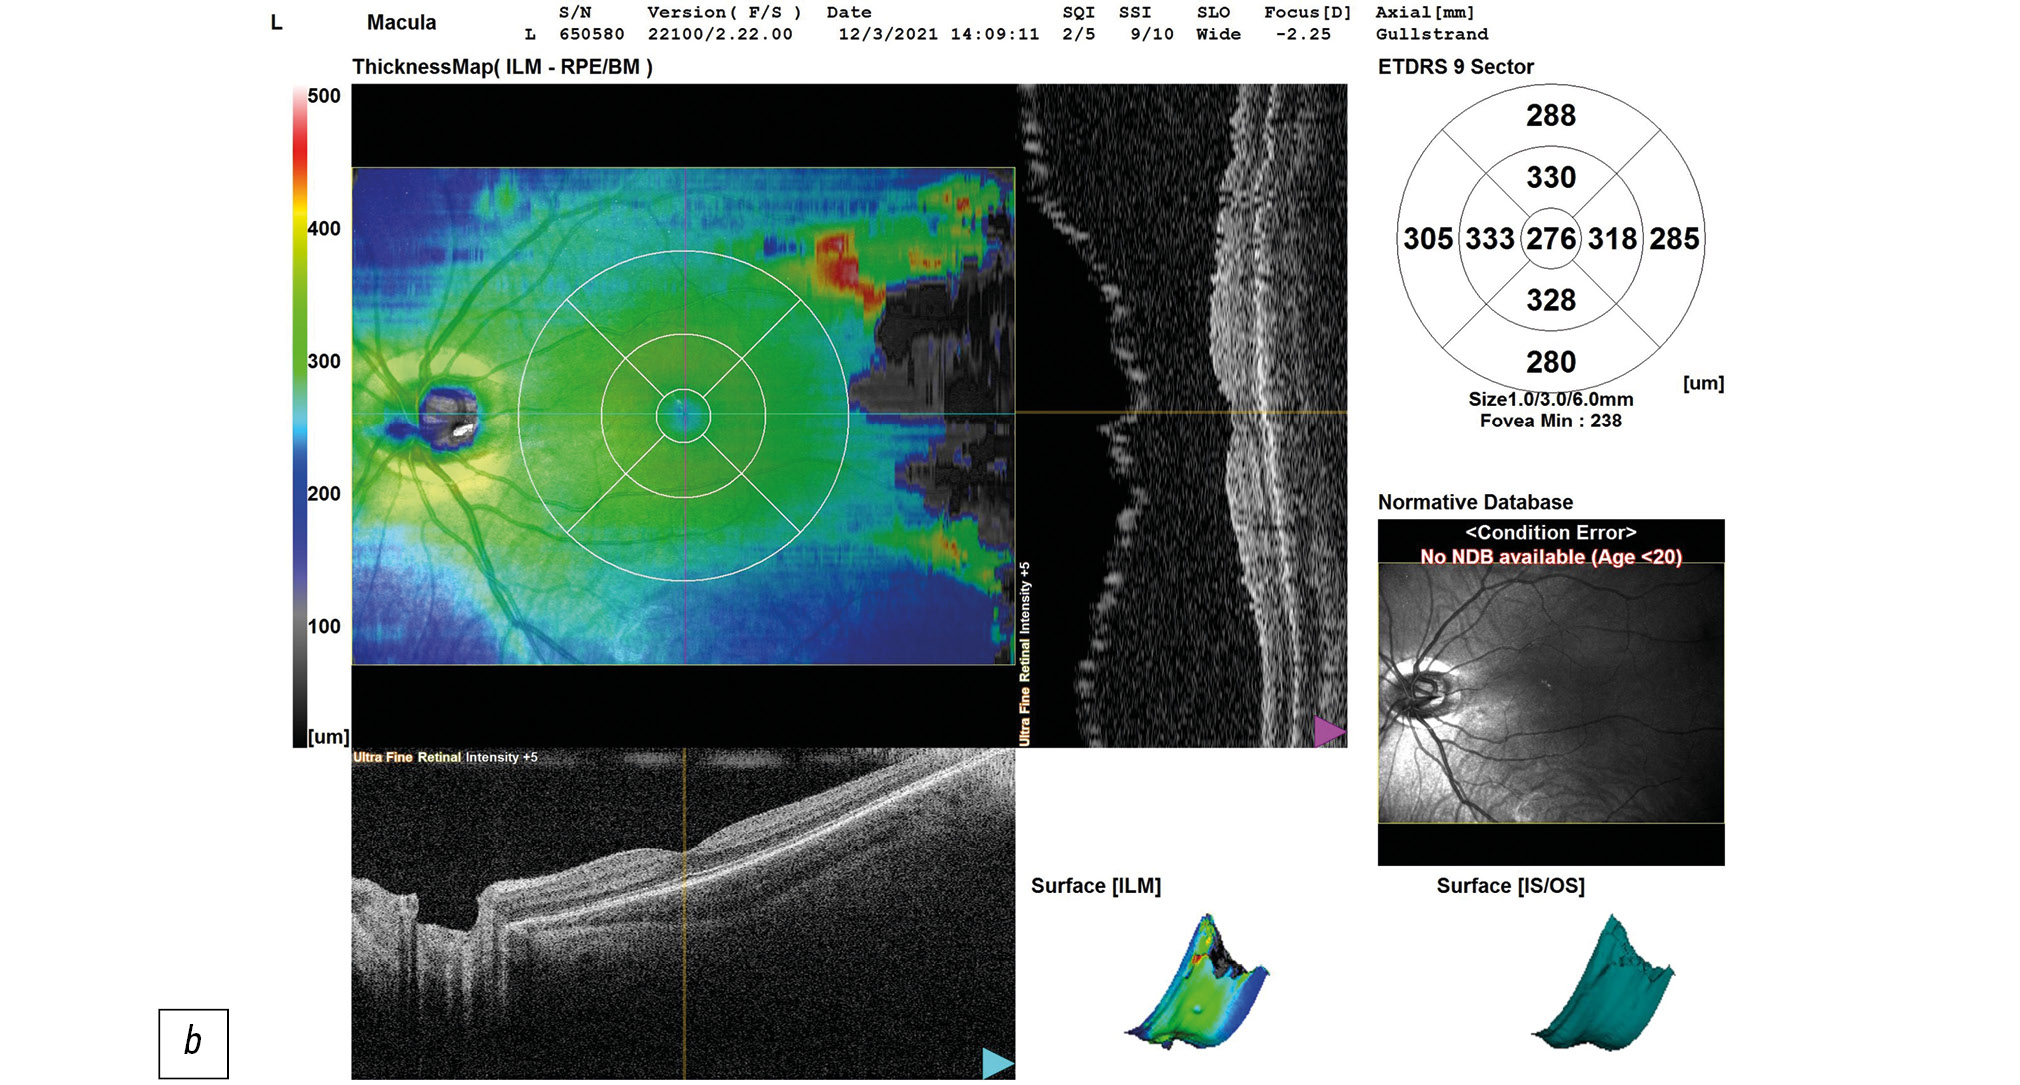

Данные ОКТ макулярной зоны сетчатки правого и левого глаз ребёнка представлены на рисунке 2. Данные ОКТ диска зрительного нерва (ДЗН) правого и левого глаз ребёнка представлены на рисунке 3.

Рис. 2, b. ОКТ сетчатки левого глаза ребёнка на момент поступления в стационар: фовеолярная депрессия выражена, структура сетчатки сохранена, центральная толщина сетчатки 276 мкм.

Справа — контур фовеолярной депрессии сглажен, отслойка нейроэпителия в макулярной зоне, деструкция и дезорганизация нейроэпителия и пигментного эпителия, центральная толщина сетчатки (ЦТС) 321 мкм, Слева — структура сетчатки в макуле не изменена, ЦТС 276 мкм. Справа экскавация ДЗН деформирована, расширена, заполнена субстратом однородной рефлективности средней степени, перипапиллярная щелевидная отслойка нейроэпителия в верхне-височном (рис. 3а) и нижне-височном (рис. 3б) квадрантах. Слева — экскавация ДЗН деформирована, расширена.